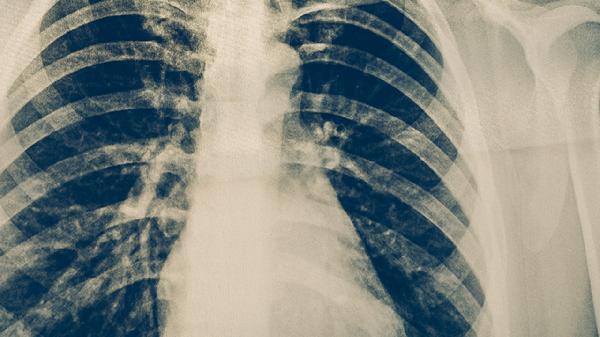

3、影像学鉴别

胸部CT是鉴别双肺感染性病变与肺癌的重要检查。感染性病变多表现为双肺多发斑片状、磨玻璃样阴影,边界模糊,可伴有胸腔积液。肺癌则常为单发结节或肿块,边缘毛糙或有分叶,可能伴随肺门淋巴结肿大。增强CT中肺癌多呈不均匀强化,而感染性病变强化模式不同。